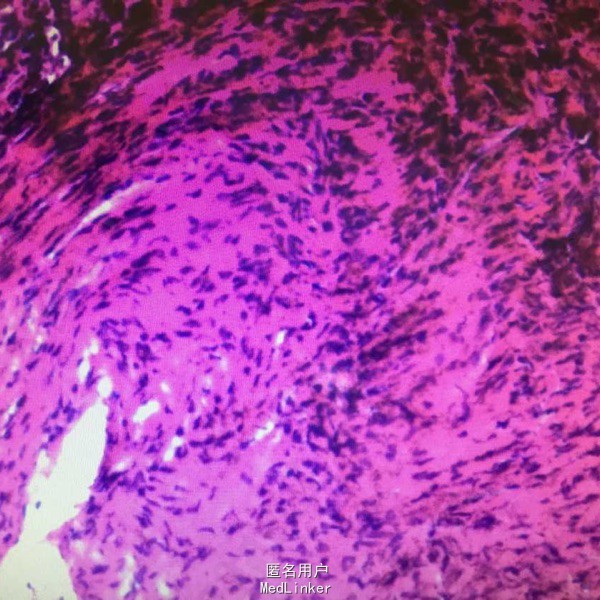

术后病理报告结为:”右股骨下段“小块增生纤维组织伴含铁血黄素沉着,片内提示结合临床及影像学考虑,干骺端纤维缺损或非骨化纤维瘤。

非骨化性纤维瘤是纤维母细胞组成的干骺端错构瘤,目前把病灶小、无临床症状、病变局限于骨膜下或皮质内的称之为干骺端纤维性缺损或纤维皮质缺损,而把病灶较大,病变可扩展侵入髓腔而且常合并病理性骨折的称之为非骨化性纤维瘤或非成骨性纤维瘤,二者均属于组织细胞纤维瘤范围,有学者认为该病不是肿瘤,而是骨发育异常,该病预后好,有些可以自愈,也可行单纯刮除,应注意随访。